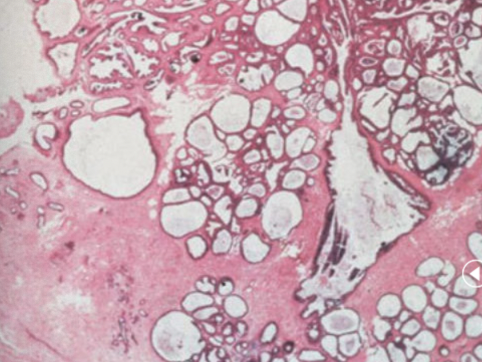

benign fibroadenoma

benign neoplasm of both the stromal and epithelial cell components of the breast. Well circumscribed, non infiltrative lesion that lacks atypia